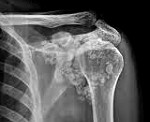

Хондроматоз суставов диагностируется на основании клинических данных, результатов инструментальных исследований, гистологического анализа синовиальной оболочки. На рентгенограммах обнаруживаются множественные шаровидные или овальные тени с четкими контурами. Однако обзорная рентгенография суставов позволяет выявить лишь внутрисуставные тела, содержащие соли кальция. Дополнительную информацию относительно количества, размеров и расположения хрящевых телец удается получить с помощью УЗИ суставов, термографии, артрографии, МРТ и КТ суставов.

- Неинвазивные исследования. На рентгенограммах обнаруживаются множественные шаровидные или овальные тени с четкими контурами. Однако обзорная рентгенография суставов позволяет выявить лишь внутрисуставные тела, содержащие соли кальция. Дополнительную информацию относительно количества, размеров и расположения хрящевых телец удается получить с помощью УЗИ суставов, термографии, артрографии, МРТ и КТ суставов.